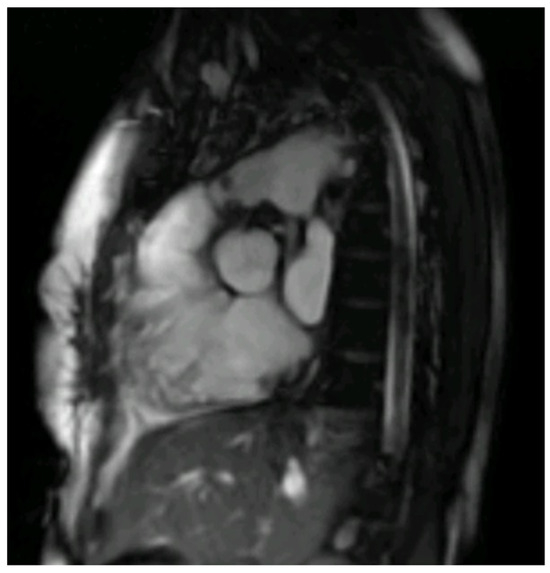

Figure 2. Right ventricle outflow tract bSSFP CMR image with endocarditis vegetation of a thirty-year-old male with Tetralogy of Fallot and a bio pulmonic conduit in the pulmonary position, with positive blood cultures for S. Mitis following dental extraction.